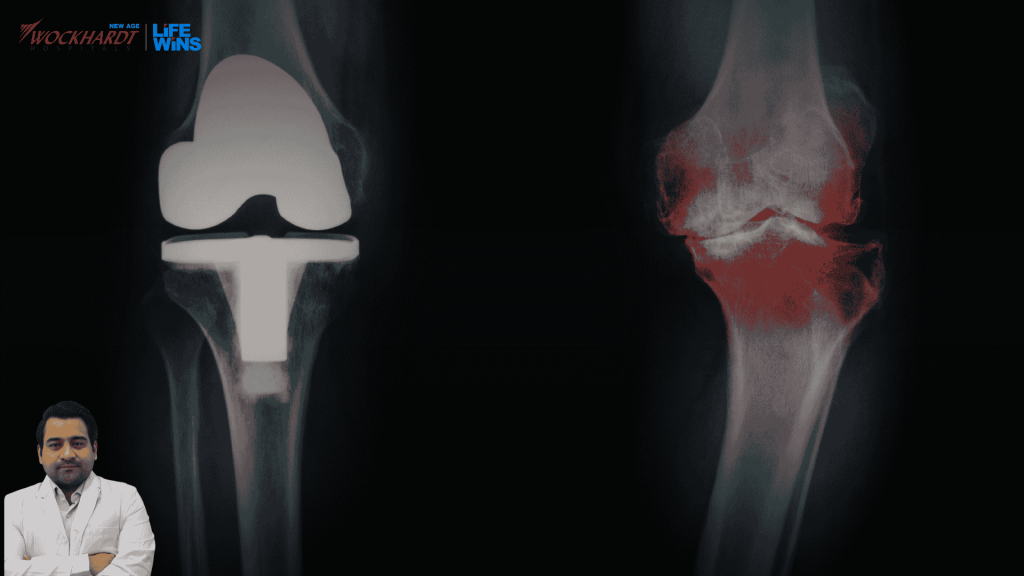

At Wockhardt Hospitals, Nagpur, AI-based robotic knee surgery has transformed a patient’s life!